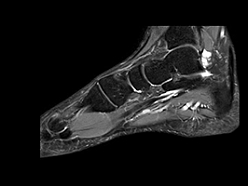

Mūsu klīnikā Teika Plaza, Rīgā, mēs piedāvājam dažādus magnētiskās rezonanses izmeklējumus gan valsts apmaksātus, gan privātus pakalpojumus. Mūsu pakalpojumi ir īpaši piemēroti neiroloģiskiem izmeklējumiem, locītavu izmeklējumiem, iekšējo orgānu analīzēm un daudzām citām diagnostiskām vajadzībām. Ar modernu iekārtu palīdzību mēs veicam izmeklējumus, kas nodrošina augstu precizitāti un atbilstību visām medicīniskajām prasībām.

Mūsu pakalpojumi aptver smadzeņu, mugurkaula, locītavu un iekšējo orgānu izmeklējumus. Mēs sniedzam detalizētus attēlus, kas palīdz ārstiem ātri noteikt diagnozi un izstrādāt efektīvas ārstēšanas metodes.